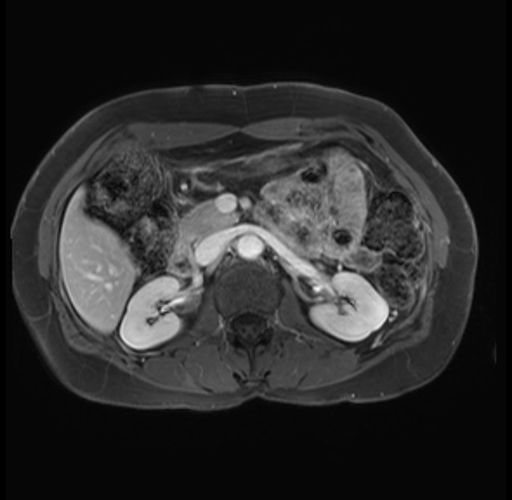

Imaging Analysis

Look through the patient's CT scan to identify any areas of concern for the necessary procedure.

Based on your CT findings, which issue(s) are present and would give reason for "planned slowing down moment(s)" in this case?